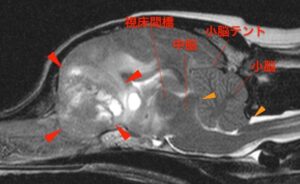

MRI検査では左の前頭部に巨大な腫瘤が認められた。腫瘤は近くの髄膜と連続しているように見えることから髄膜腫が最も疑われた。

この患者さんでは腫瘤が周りの組織を大きく圧迫し、脳が広く浮腫んでいた。

頭の中は閉鎖空間のため、圧の逃げ場がなく、腫瘤や浮腫みにより脳圧が高くなると脳が本来の場所から逸脱し(脳ヘルニア)命に関わることがある。